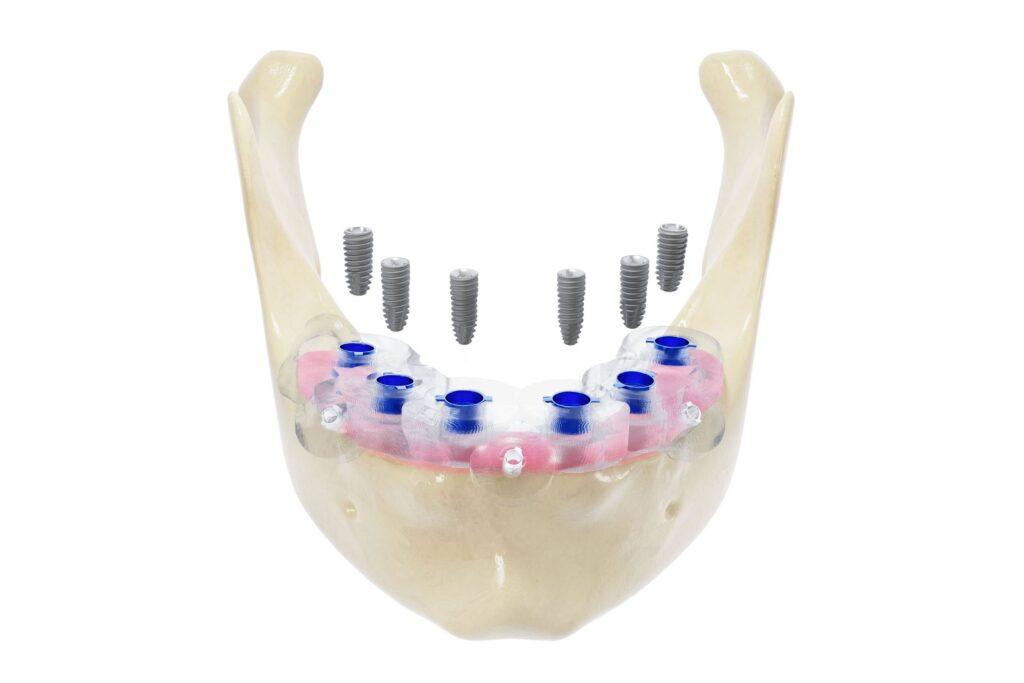

二、All-on-6 強化型全口重建

技術原理

在All-on-4基礎上,加裝2根植體,提高支撐力與穩定性。

適合對象

- 咬合力強者(愛吃硬食)

- 想要耐用更長久者

- 骨質條件較好者

優點

- 分擔咬力更平均

- 成功率更高

- 適合高需求族群

缺點

- 費用較高

- 需足夠骨量